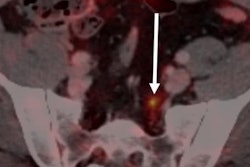

CT, Ga-68 PSMA PET/CT, and F-18 FMC PET/CT were performed in 39 patients between January and April 2015, and the scans were evaluated by experienced nuclear medicine physicians blinded to which approach was used. Morigi and colleagues evaluated the scan results and their impact on patient management. Of the subjects, 89% had only their prostate gland removed in prior treatment, while the remaining 11% had radiation therapy (JNM, August 2015, Vol. 56:8, pp. 1185-1190).

Even at very low PSA levels (< 0.5 ng/mL), Ga-68 PSMA PET/CT was able to detect sites of possible recurrence in 50% of the patients, while F-18 FMC PET/CT detected possible recurrence in only 12.5%. PSMA also strongly influenced patient management in the cohort (63%), with an added value over FMC in 44%, the researchers found.